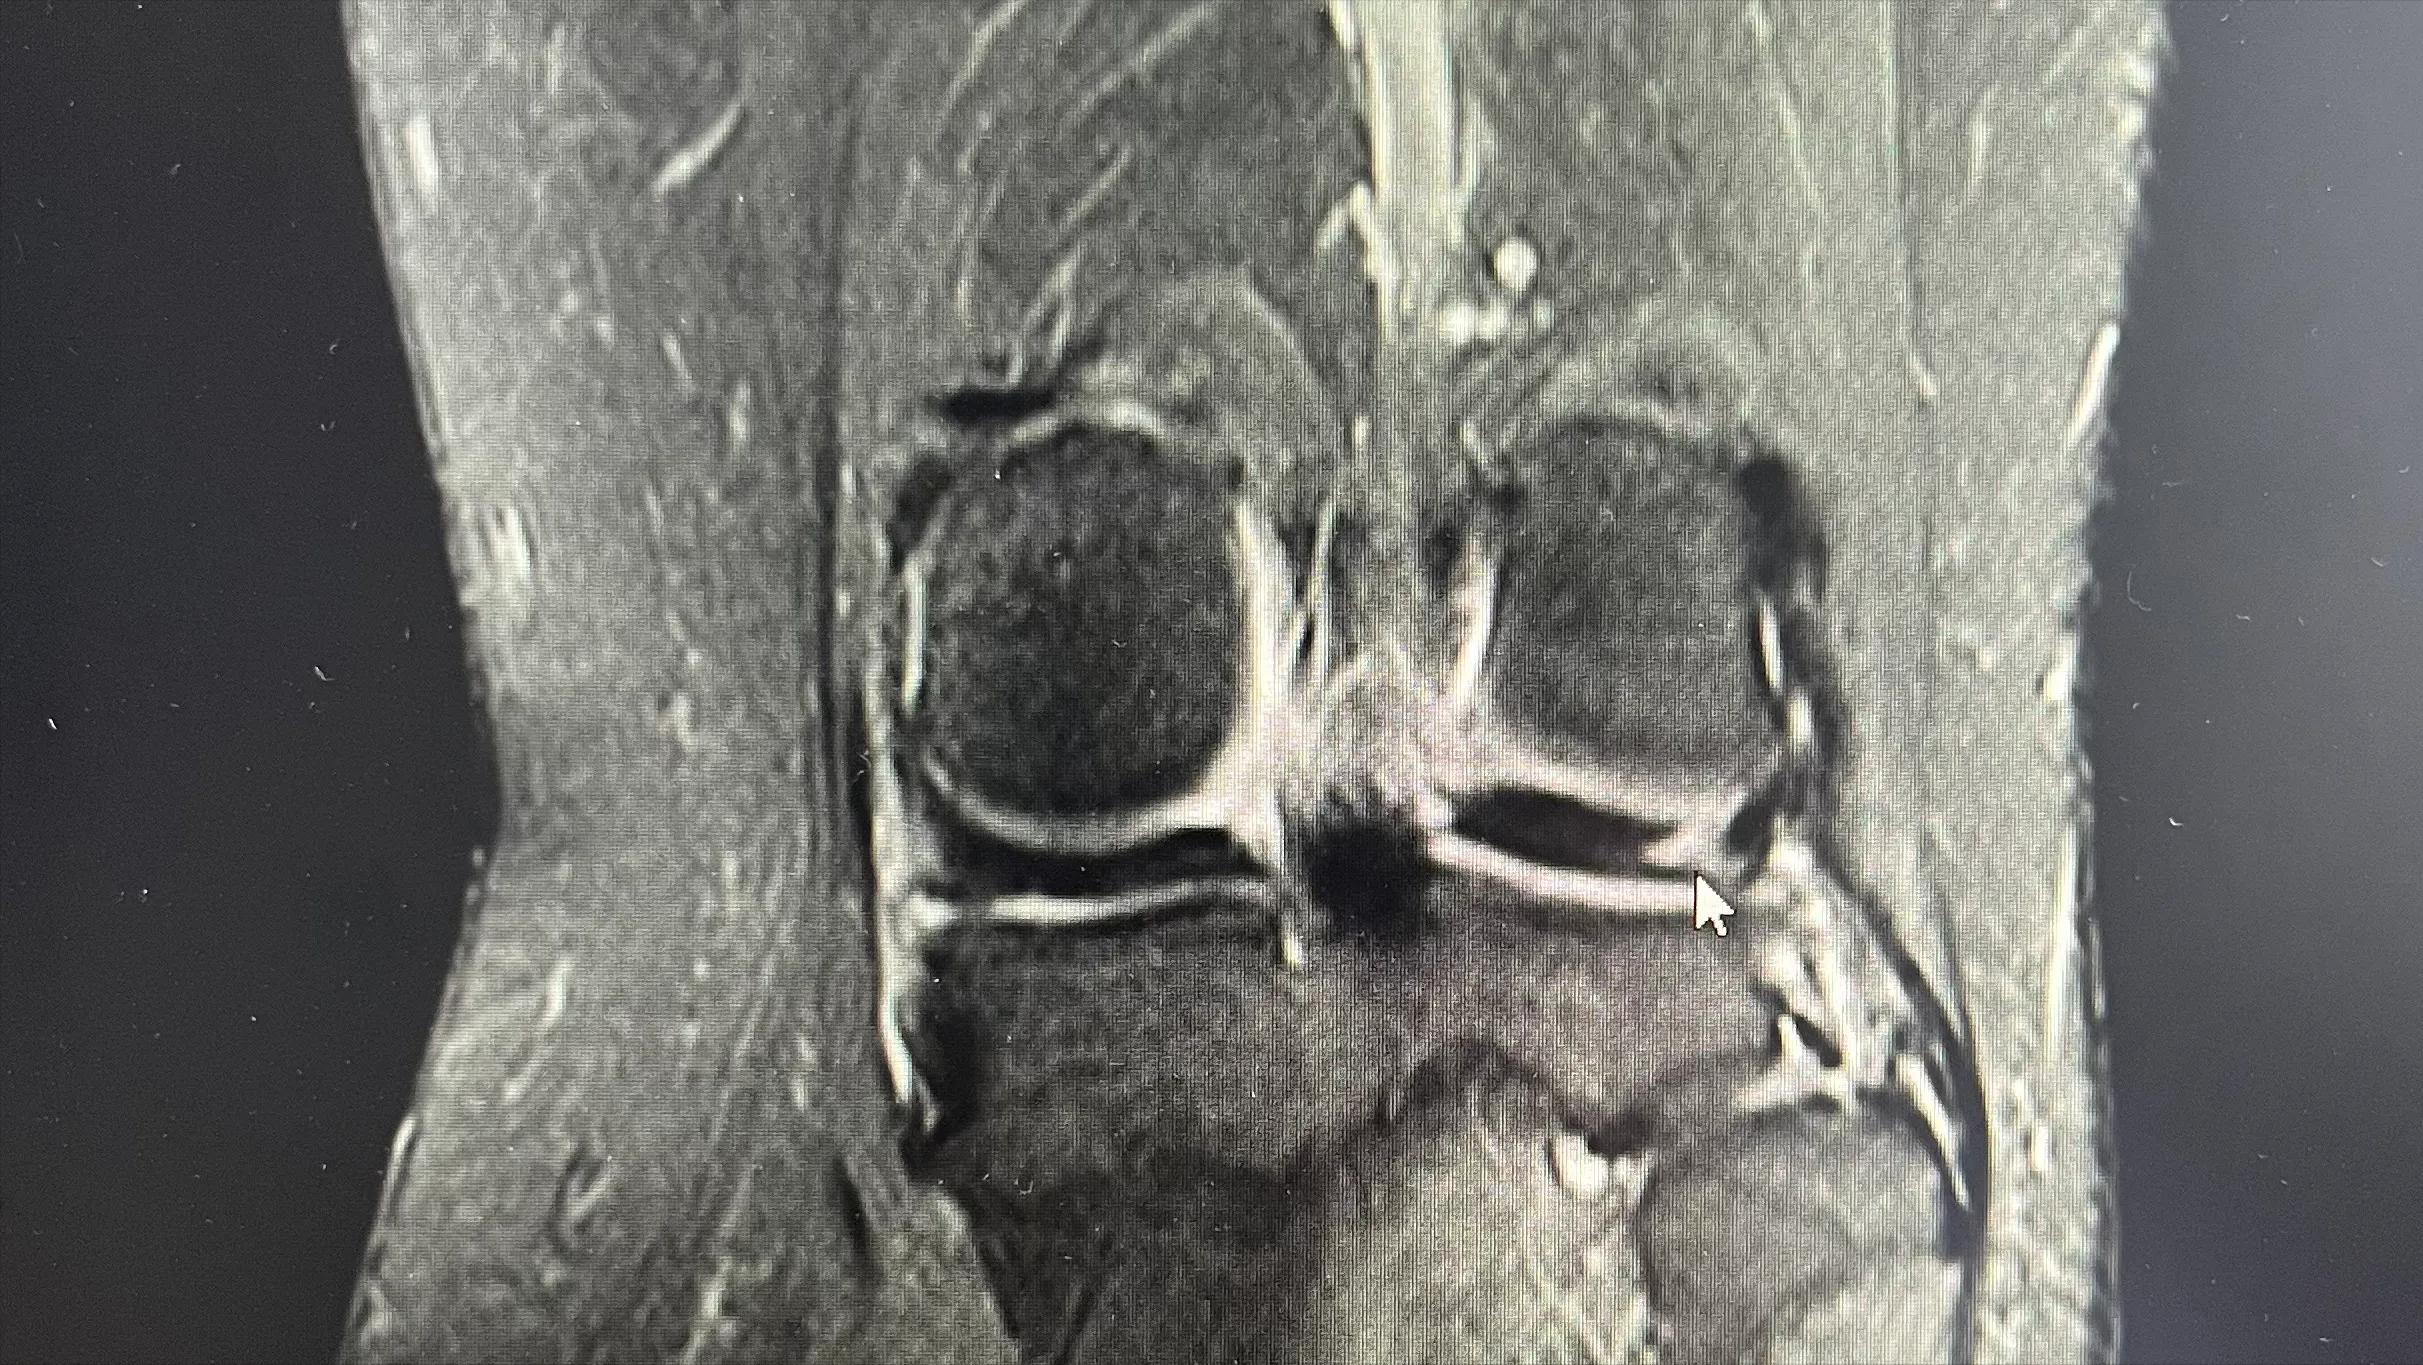

2022.5.2再次磁共振报告

半月板的轻微损伤要注意什么,半月板损伤两年多了最好的方法

再次磁共振检查光标处显示有愈合迹象

陈女士非常纠结,不知道怎么办好,最后到了我们科室,我们根据她的具体情况制定了治疗方案,以两周的保守治疗作为一个铺垫,若效果不佳则行手术治疗,手术后继续康复治疗度过恢复期。最终经过规范的康复保守治疗,陈女士的膝关节得到了快速的康复 ,最终两周保守治疗达到了预期效果避免进一步手术治疗,门诊后期复查发现半月板损伤也从三度转变成二度损伤,进一步说明保守治疗也是一个不错的选择。